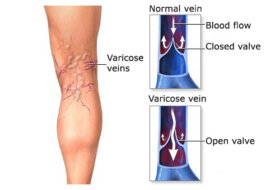

보기에도 흉한 정맥류는 보통 다리에 생기지만 얼굴에도 생길 수 있다. 특히 여성들은 정맥류가 생기면 더 신경이 쓰인다. 정맥류가 발생하는 원인으로는 임신,…